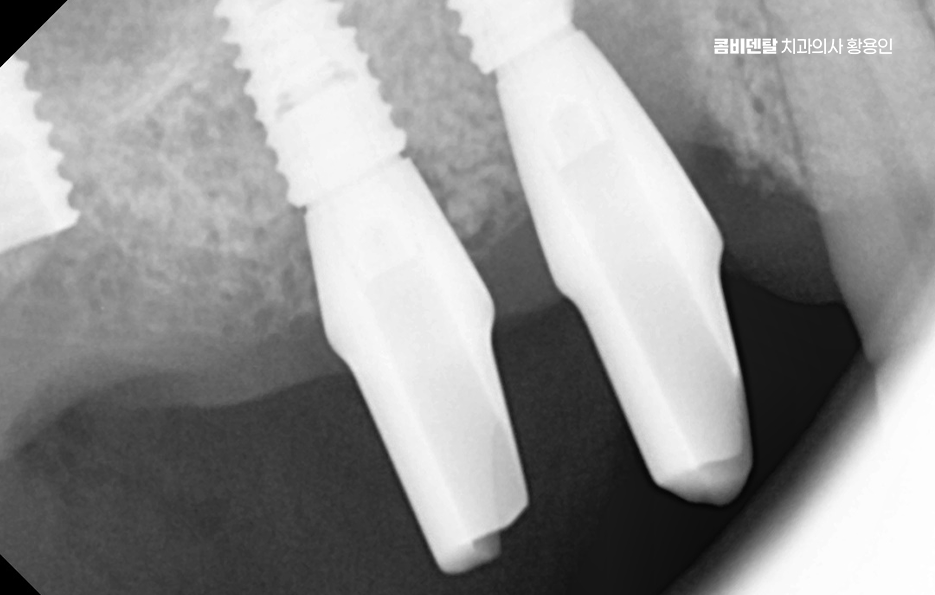

나에게 맞는 치료를 하기 위해서는 정확한 진단과 설계가 중요하며 CT 촬영 등을 통해 신경 위치, 뼈의 양, 두께 등을 정밀하게 진단한 다음, 교합과 치열 구조에 맞는 위치에 임플란트를 심는 게 중요한데 잘못된 위치에 심어지면 오래 쓰기 어렵고, 나중에 통증이나 염증이 생길 수 있었어요.

임플란트는 처음 수술보다 이후 관리가 더 중요하다고 할 정도니까, 처음부터 잘 설계된 치료계획 아래 수술을 받는 게 중요하며 그 이후로도 사후관리를 잘하는 것이 곧 임플란트의 수명 유지에 중요한 거예요